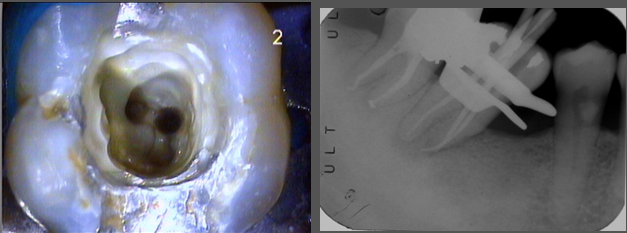

C形根管修形,以顯微鏡輔助使用

研究報告東方人的下顎第二大臼齒的C形根管大約有3成,這位患者有二次蛀牙,因此進行根管治療,使用顯微將根管徹底清潔並封填之,術後情況良好